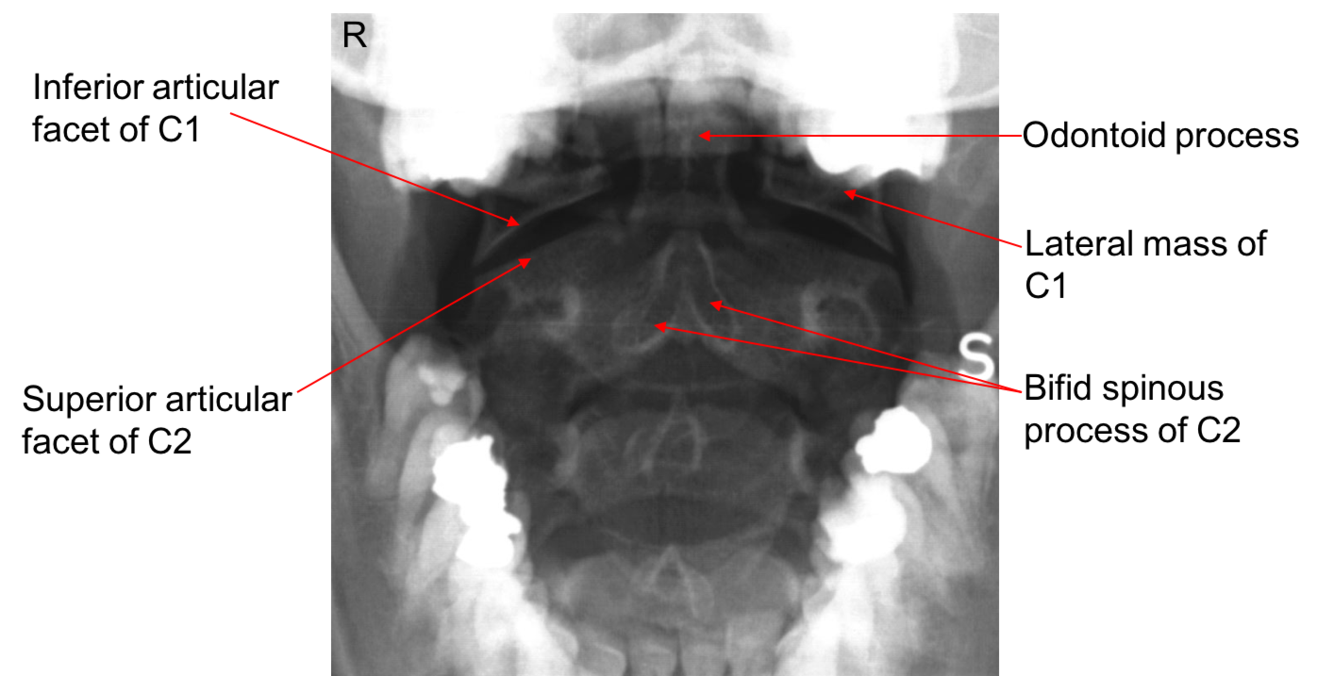

Label this image